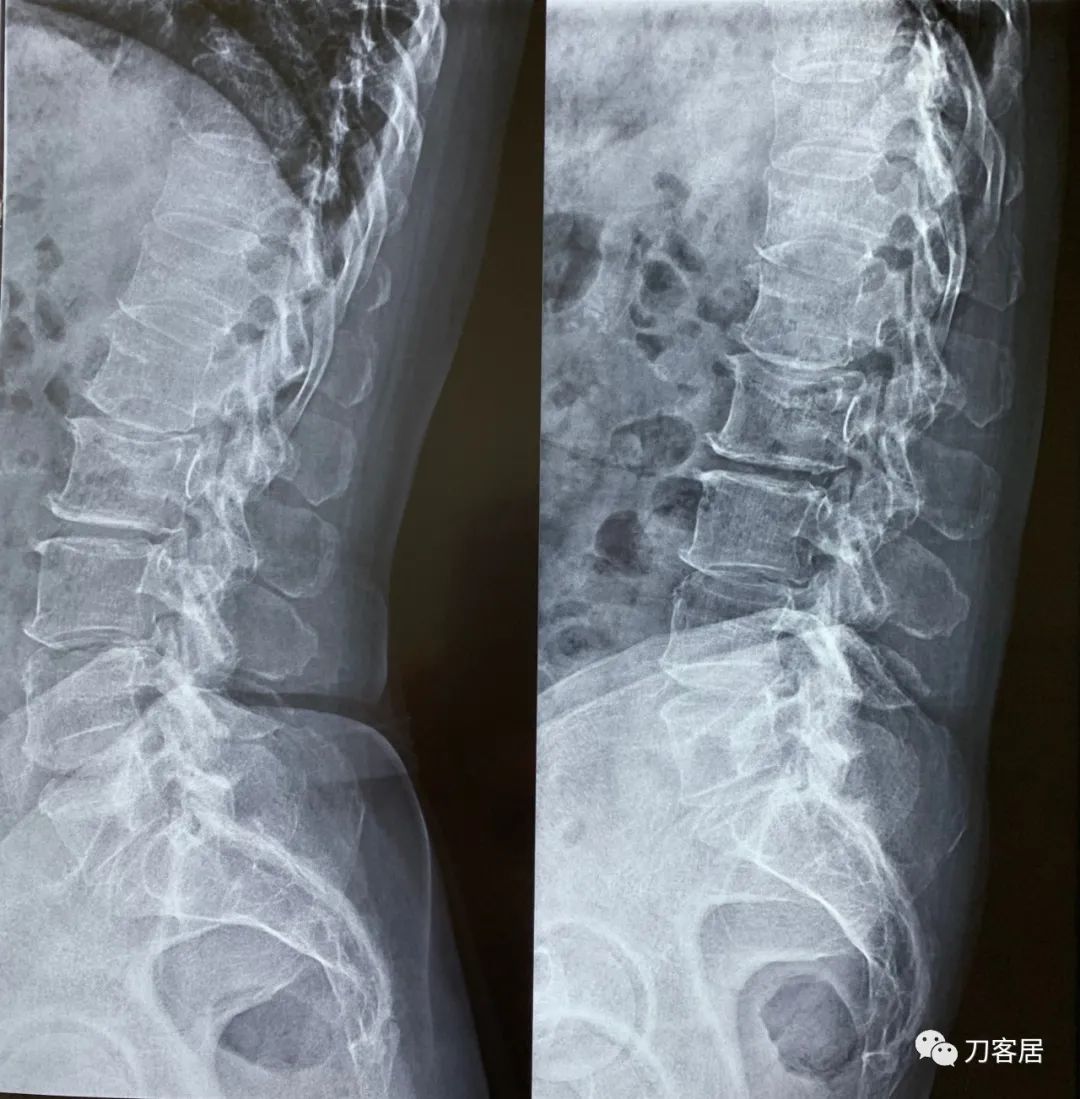

2021年12月12日去渭源县医院做颈椎腰椎MRI,提示1.腰椎侧弯畸形并骨质增生,2. L5S1椎体终板炎(I型), 3. L1-S1椎间盘变性并腰2-4,腰5骶1椎间盘膨出,腰4-5椎间盘突出并相应平面继发性椎管狭窄。2020年12月中旬于渭源县医院行骶管注射2次6针后睡眠改善,

2021年5月17日,西京医院骨科门诊找我就诊,自带影像学检查资料提示腰椎侧弯,腰3-4,腰4-5椎间盘突出,黄韧带肥厚,椎管狭窄。

建议其查双光子骨密度,骨盆正位片以及腰椎间盘平扫。腰椎正侧位X线片以及动力位片,站立位脊柱全长正侧位X线片,以了解其是否有骨质疏松,并了解脊柱侧弯情况,腰椎局部X线表现情况和腰椎间盘突出和椎管狭窄情况。

从这个患者的影像资料分析,颈椎间盘突出问题不大,没有明确的上位神经元损伤表现,所以,不考虑颈椎和胸椎问题。腰椎侧弯畸形,但不严重。因为存在腰椎侧弯,使得腰椎MRI在扫描切面的时候,显示的椎间盘突出或椎管狭窄会有一定的误差,所以,又加做了经椎间盘的CT平扫,影像表现并不严重,综上,腰椎间盘突出,腰椎管狭窄,腰椎侧弯,不考虑手术治疗。同时,患者的主要痛苦是心理疾病,而不是器质性疾病,所以,以心身疾病治疗为主。虽然患者骨密度检查结果提示正常,但X线片显示骨质疏松,且其症状也与骨质疏松的症状有符合之处,比如静息痛,不能入睡,动作及姿势变换时痛加重等,所以,给予实验性抗骨质疏松治疗,以观疗效。